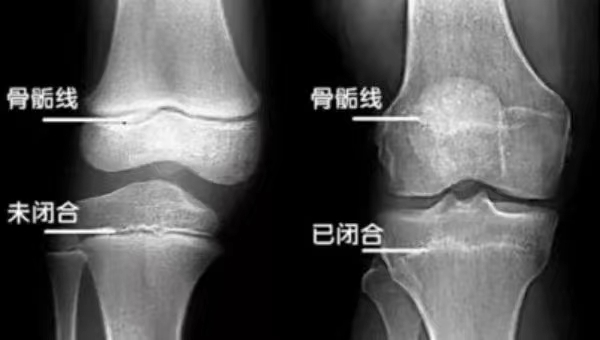

骨龄检测要定期,身高问题要重视。人的生长发育可用两个“年龄”来表示,即生活年龄(日历年龄)和生物年龄(骨龄)。骨龄是人体骨骼年龄简称,代表骨骼成熟度,需要依据骨骼在X线摄像中的特定图像来确定,通过拍摄左手腕部X射线片,分析骨化中心出现的时间、数目、形态及变化以及干骺端愈合程度等发育趋势来评估。

骨龄未闭合的骨龄图

骨龄已闭合骨龄图